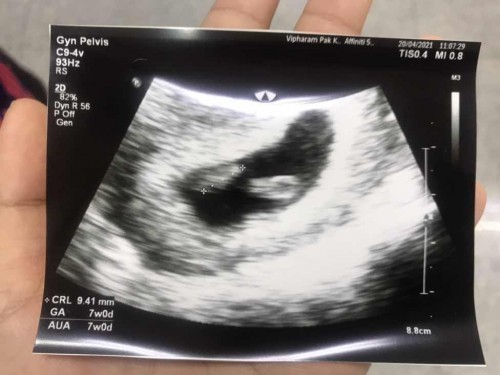

แบบนี้ท้องแฝดไหมค้าาา.

ตอนนี้น้องหัวใจเต้น1 คนอีก1คนยังไม่เต้น เพราะ1 อาทิตย์ที่แล้วซาวเจอน้องแค่1 คนค่ะ รอผลซาวอีกที่วันที่26 นี้ค่ะ แต่อิแม่ลุ้นสุดๆอยากได้แฝดมากค่ะเพราะแม่ก็เป็นแฝดค่ะ 🥰